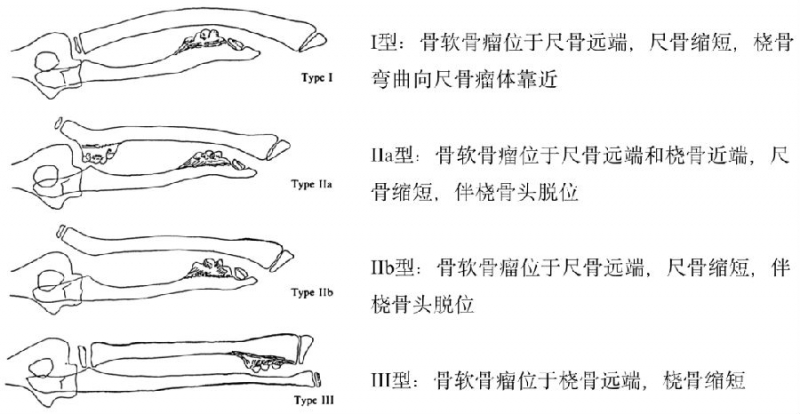

因此,构建针对性的临床分型是帮助手术方式选择及提高术后疗效的有效手段。1989年,日本大阪大学医学院Masada等研究报道了一种适用于MHE致前臂畸形的临床分型(I、IIa、IIb、III型),被广泛接受并沿用至今(图2)。

图2. MHE前臂畸形-Masada分型